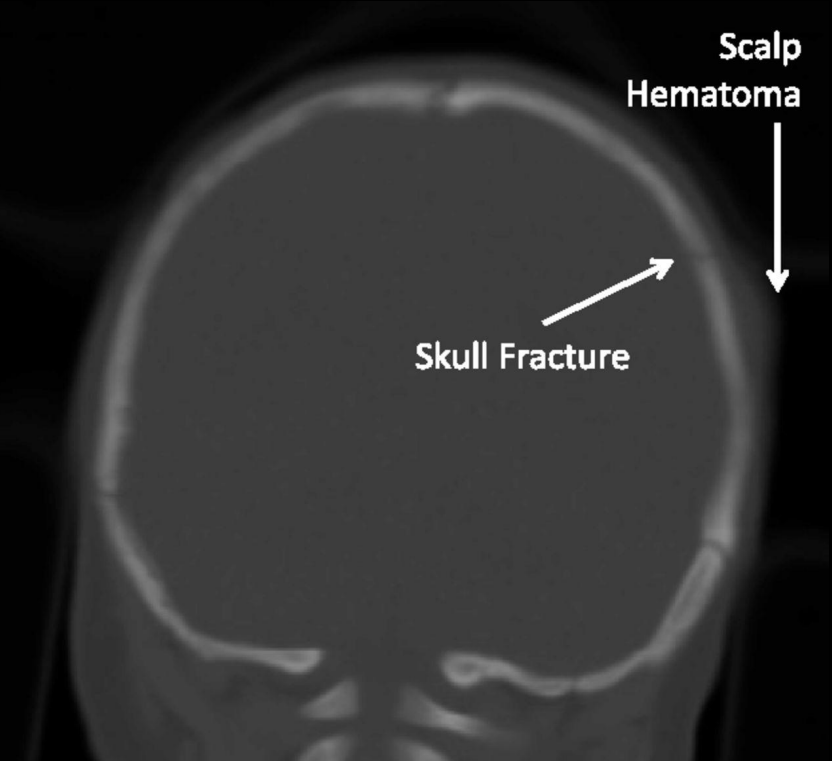

Fractura lineal: hallazgos

Línea radiolucente fina; temporal/parietal + frec

Fractura deprimida: imagen clave

Hundimiento del hueso; mejor en TC 3D.

Frontoparietal